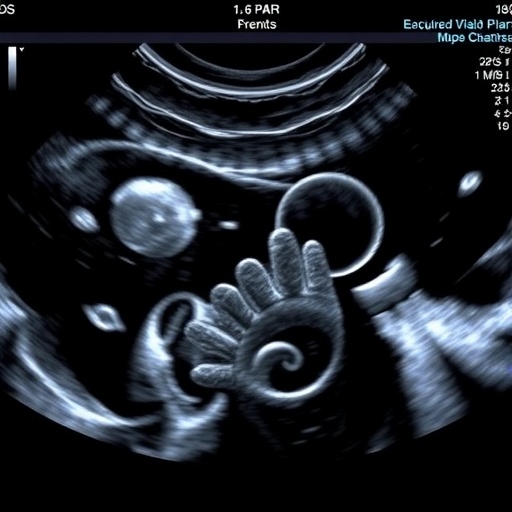

Ultrasound, a technology widely employed in various medical disciplines, offers an unparalleled advantage in neonatal intensive care units (NICUs) because of its safety profile and ability to provide immediate, detailed visualization of soft tissues and blood flow. The protocol developed by Aoki and colleagues leverages advanced Doppler ultrasound techniques to continuously monitor the blood flow velocities in cerebral arteries and veins, allowing clinicians to detect early signs of circulatory instability that may precipitate IVH. This capability enables precise and timely adjustments in circulatory management tailored to the infant’s current physiological state, a step beyond conventional static assessments.

Intriguingly, the research also highlights the differential vulnerability of cerebral vasculature in extremely preterm infants. Their blood vessels, particularly those in the germinal matrix region, lack the structural integrity of more mature vessels, making them susceptible to rupture under stress. Ultrasound imaging enables clinicians to visualize these vulnerable areas in high resolution, potentially identifying infants at greater risk and warranting heightened surveillance or pre-emptive intervention. This represents a personalized medicine approach in neonatal care, tailoring treatment strategies to each infant’s unique cerebral hemodynamics.